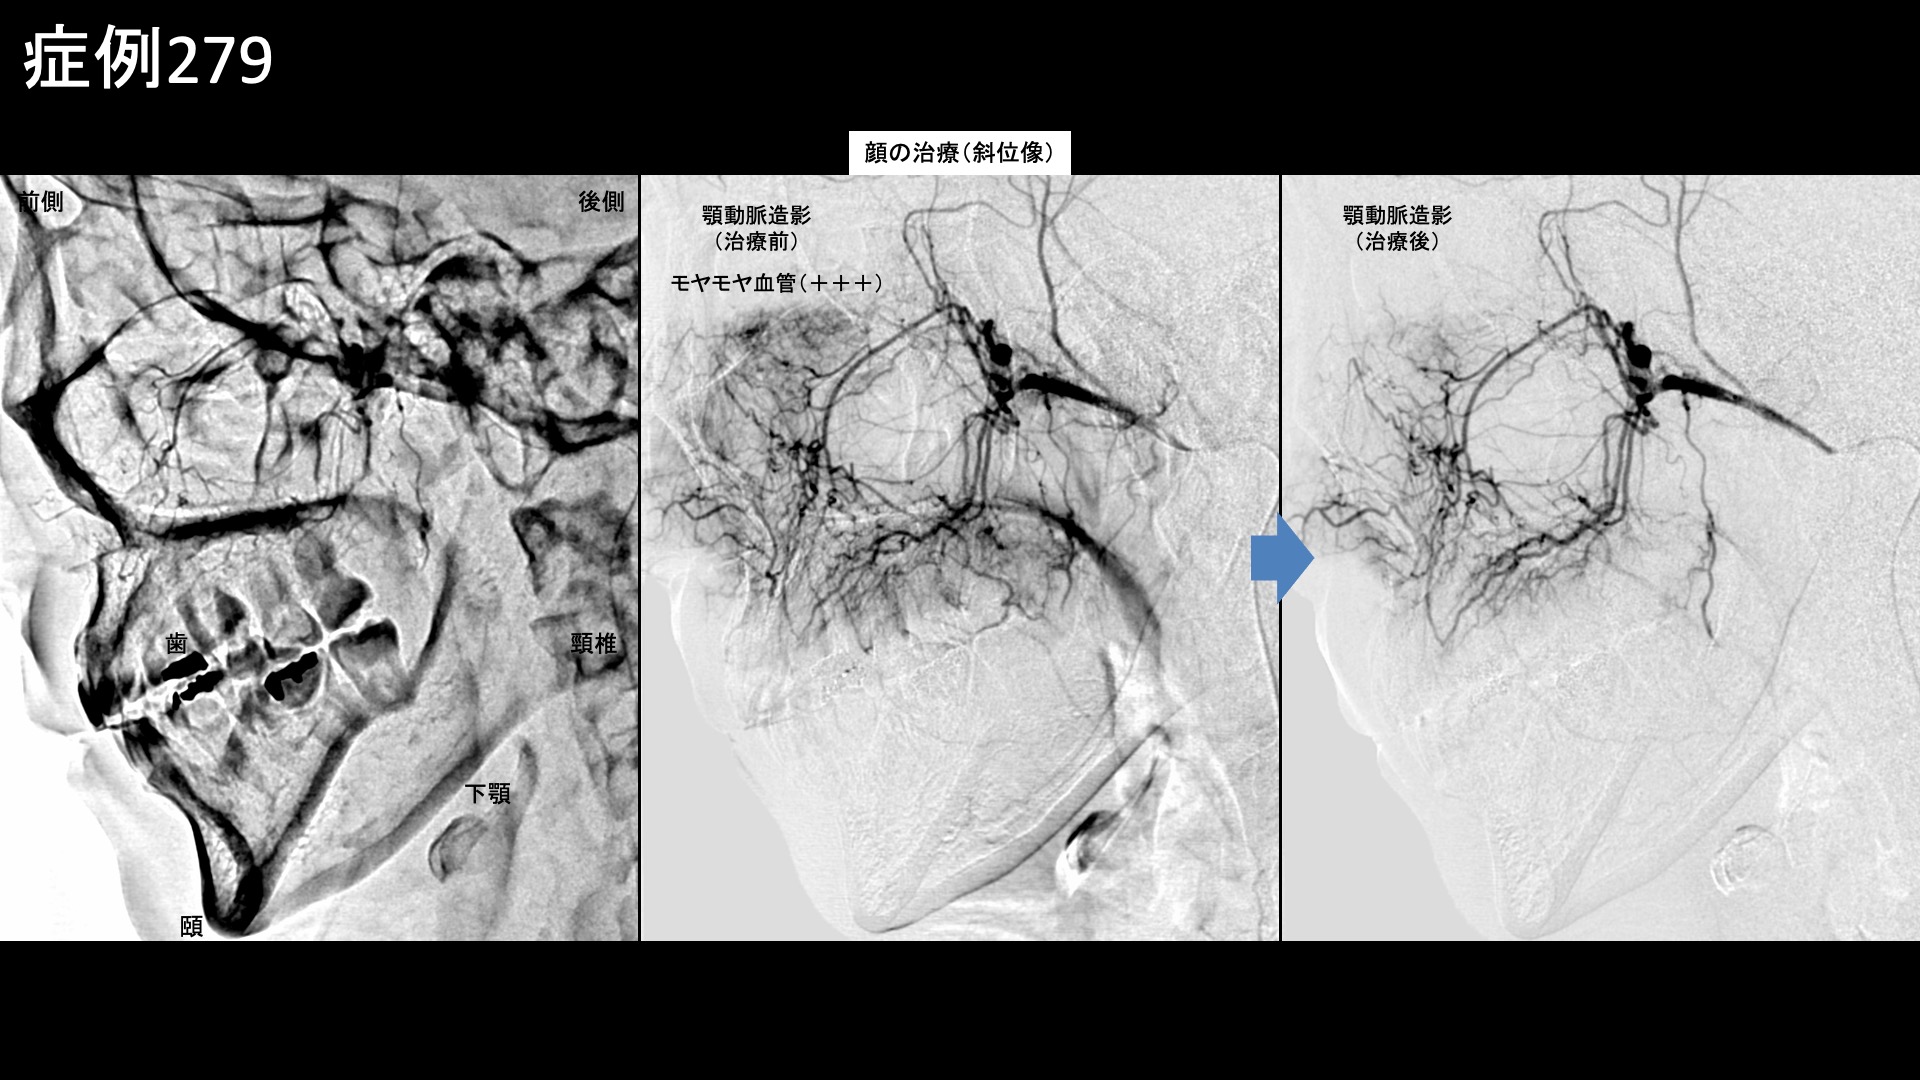

顎や口の周囲などに分布する顔面動脈、頬の主要責任血管である顎動脈で特にモヤモヤ血管が濃染像として描出されました。治療後は画像上速やかに消失しました。その他複数箇所の治療を行い終了しました。

治療前画像:損傷を受ける、あるいは繰り返しのストレスにより発生した異常な新生血管

治療後画像:カテーテルを用いて塞栓物質を血管内に投与し新生血管を塞いだ状態